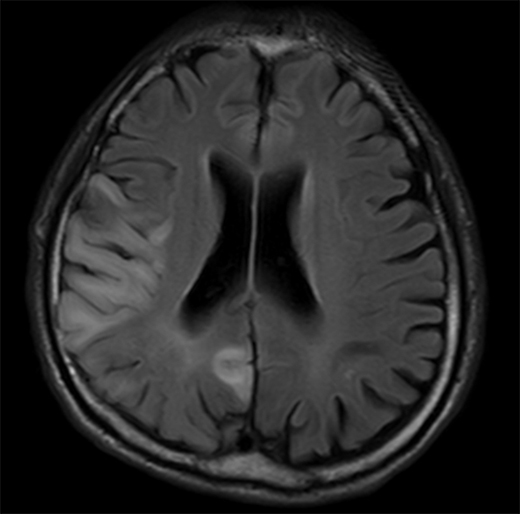

MELASはミトコンドリア病の中でも最も頻度の高い病気の一つで、低身長、全身の筋萎縮、難聴、糖尿病、頭痛、てんかん発作、乳酸アシドーシスなどいろいろな症状を呈しますが、最も特徴的な症状は反復する脳卒中様発作です(図3)。脳卒中のように突然、言葉がしゃべれなくなったり、視野の半分が見えなくなったり、手足が麻痺するなどの症状を呈します。こうした脳卒中様発作を繰り返しながら、身体機能や認知機能の障害が蓄積していきます。MELAS患者の約80%はミトコンドリアDNA(mtDNA)がコードするロイシンというアミノ酸を運搬するtRNALeu(UUR)遺伝子の一塩基変異A3243Gが原因です。この変異があるとロイシンtRNAアンチコドンのタウリン修飾が欠損し、UUGというコドンが認識されなくなり、ミトコンドリア蛋白が正常に合成できなくなります(図2)。